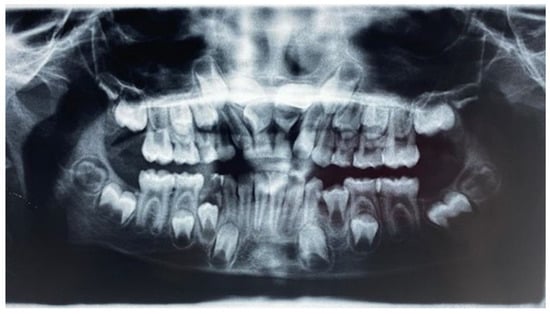

- Ortopanthomography X-ray (OPG X-ray) to evaluate the problem in relation to the entire arch, adjacent tooth and the staging of the eruption of the other dental elements.

2. Case Report

2.1. Clinical History

2.2. Clinical Exams and Diagnosis